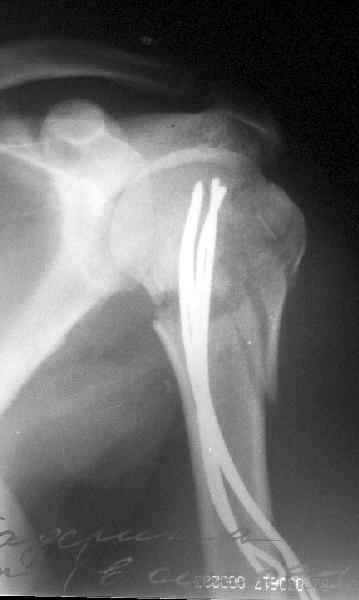

Сегодня взял больного повторно в операционную, не скажу, что повторная репозиция через неделю после первой попытки, была простая.

После удаления спиц попытался манипулировать отломками, но безуспешно, поэтому пришлось пользоваться периостальным элеватором, чтобы устранить смещение отломков и перепровести спицы. Проверил и перепроверил стабильность фиксации под ЭОПом, завтра Рг- будет готов, вот и поглядим....

Что-то, наверно, сделали мы не совсем оптимально, поскольку у Анатолия Федровича и его соратников как-то красивее "раскрываются" спицы в головке плеча - надеюсь, он прокомментирует и подскажет, что надо подправить.